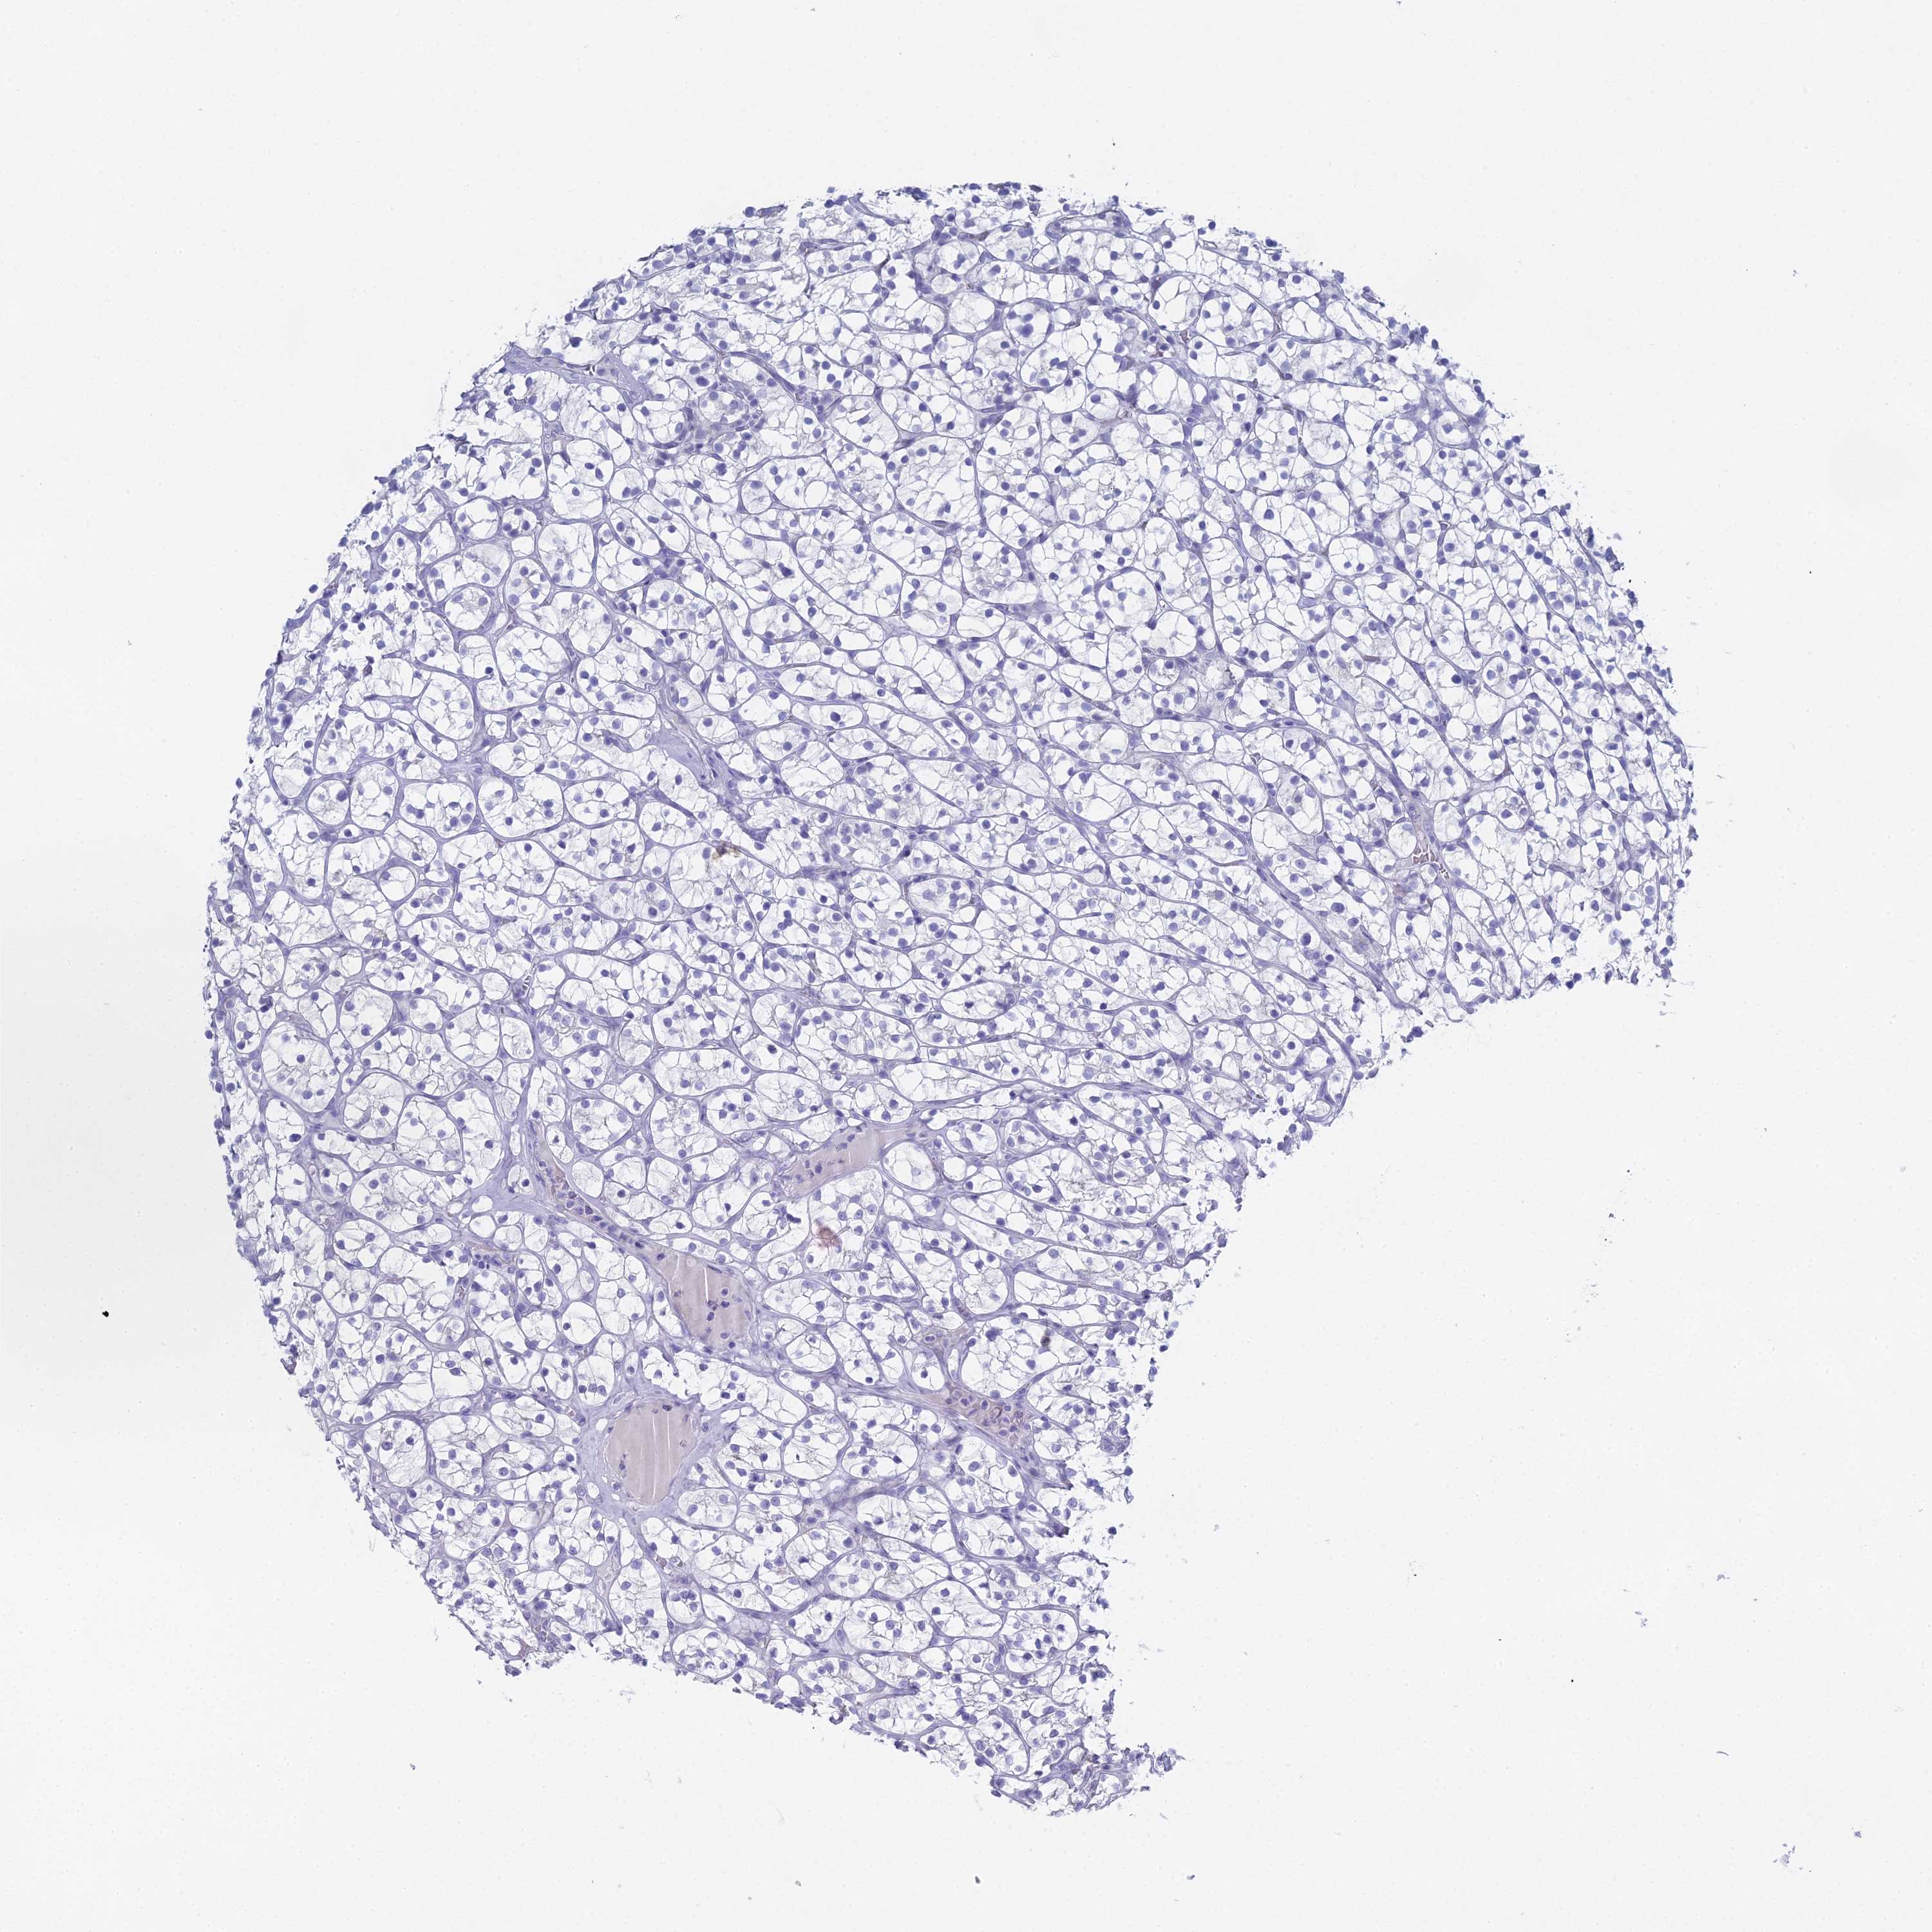

CANCER RENAL CANCER Show tissue menu

KICH TCGA KIRC TCGA KIRC VALIDATION KIRP TCGA PROTEIN RCC CPTAC PROTEIN EXPRESSION